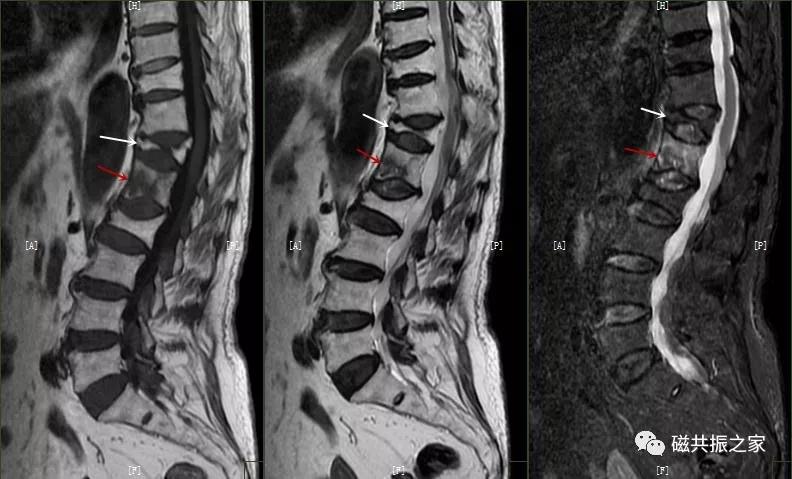

8.椎体骨折

椎体压缩性骨折常成前窄后宽的楔形改变,新鲜骨折(红箭头)常在T1WI呈低信号(出血时可呈高信号),T2WI呈低、中信号,在脂肪抑制的T2WI上呈高信号。椎体陈旧性骨折(白箭头)信号类似于正常椎体信号。如需了解脊柱骨折分型请查阅脊柱骨折的分型。